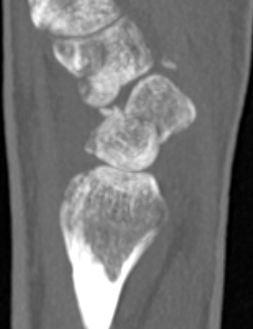

Scaphoid waist fracture 1 mm displaced

Scaphoid fracture with significant displacement

Scaphoid proximal pole fracture